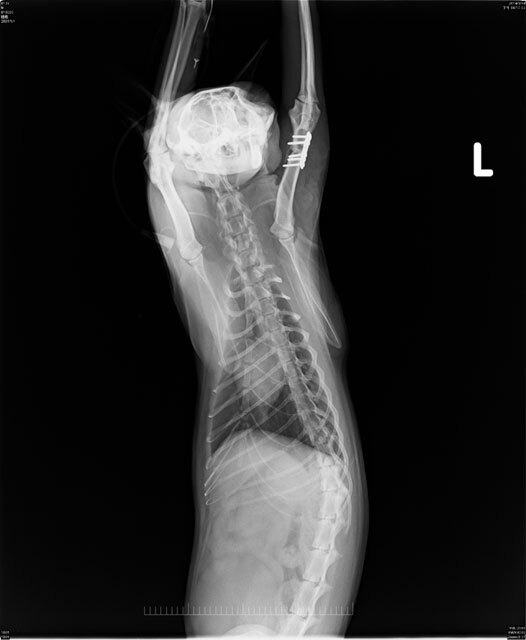

主題: 被人打斷腳的跛腳貓 申請者姓名: 陳世芬 花色: 申請日期: 2014-03-24 22:23:45 申請者部落格: https://www.facebook.com/fandy.chen 申請者臉書網址: http://blog.xuite.net/niblackcat/blog 所在縣市/合作醫院: 高雄市/銀星動物醫院 治療費用: 15200元 需求人數: 17人 已結案 (2014-05-18 09:39:47) 報名人員: 胖胖 x2(已付款)、屏東阿咩家(已付款)、機車寶(已付款)、JasmineC x2(已付款)、吳哆(已付款)、Lanny Shieh(已付款)、Chen Ping(已付款)、CHIU、yuki x3(已付款)、Ed Tsai(已付款)、lavinia x3(已付款)、思惟宗道(已付款)、 候補人員: 動物病情說明: 我在3/9救了一隻跛腳貓,是我餵養區域結紮的TNR貓咪,左前腳受傷,腳掌反折,三隻腳用跳的行動,疑似被人打斷腳,送至動物醫院,做了血檢和x光檢查,貓咪上半肢骨折,下半肢腳掌神經受損,目前有微弱反應。3/10和3/11看了五家醫院,醫生說貓咪還有機會可以把骨頭位置接回,可做骨頭重建手術,但神經受損部分需術後觀察才能知道,如果不做手術,姿勢不對,未來可能會腳拖地受傷,到時候就要截肢。

貓咪3/14在銀星動物醫院完成手術,3/24出院。